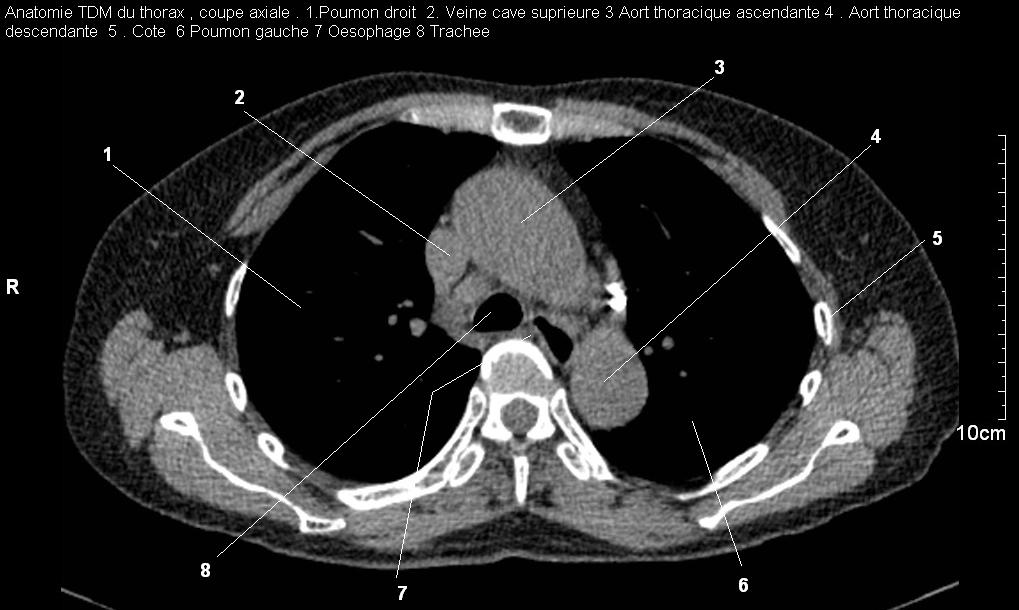

Radioanatomie pulmonaire ( image radiologie

thoracique normale )- La Tomodensitometrie du thorax (

coupes axiales fenetre mediastinale ) |

Les fenetres mediastinales permettre

d'etudier anatomie du mediastin , les structures vasculaires

en coupes axiales de 0,5-1cm sur le thorax . Ceux qui

s'installent travers le thorax de C4 a L1, L2

a n'a pas de contrast et se donnent des resutats

suivantes : |